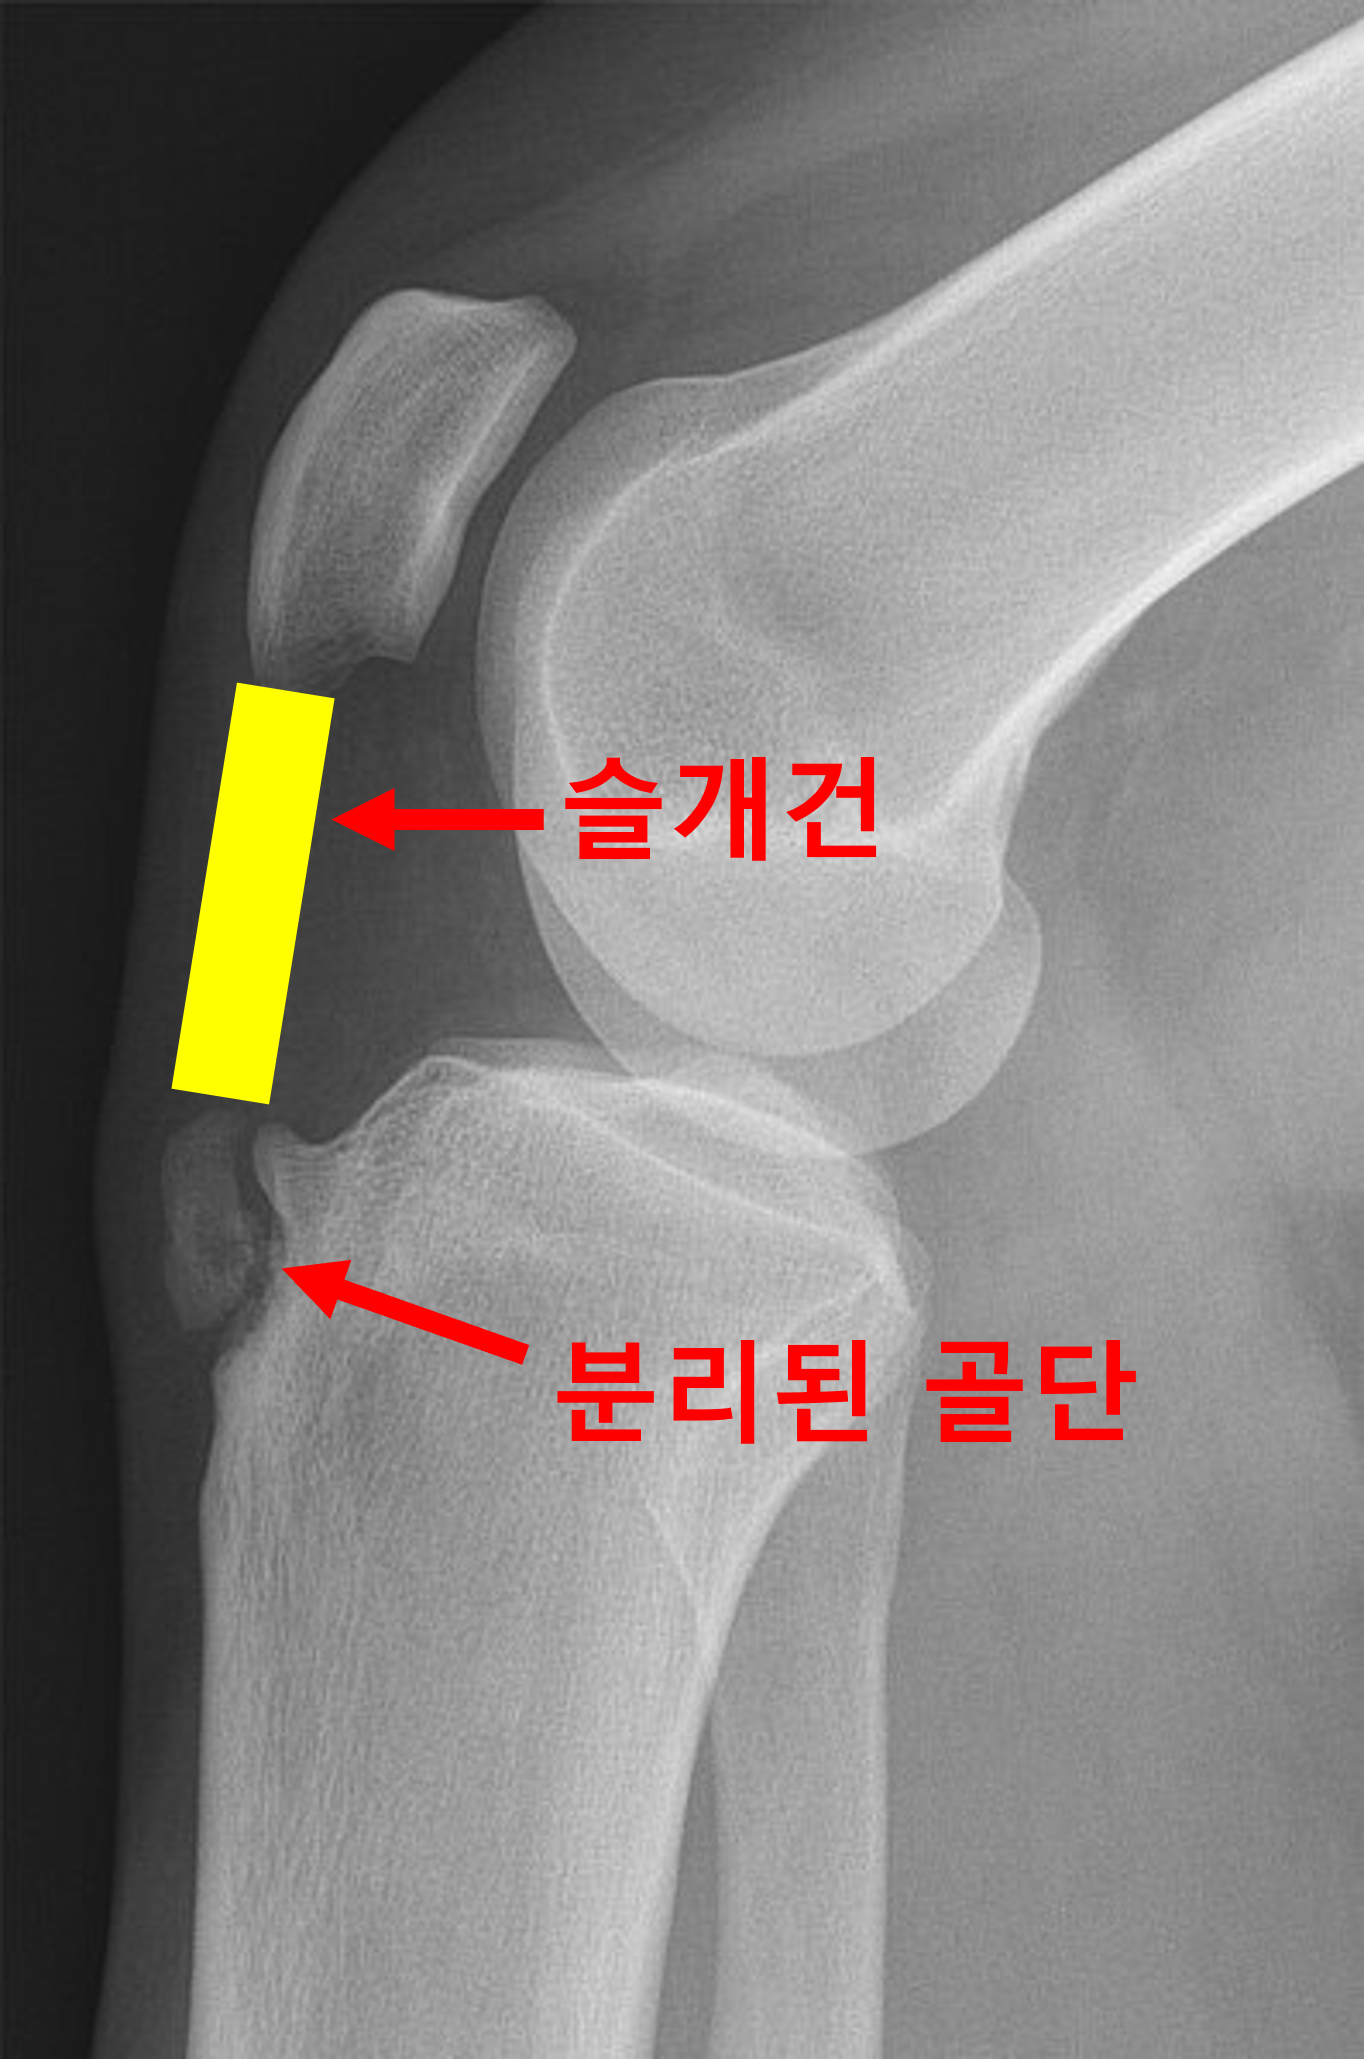

오스굿씨 병의 초기 환자에서는 분리된 골편이 불규칙하게 일부는 붙어있고, 일부는 떨어져나와 보이는 등 균일하지 않은 경계면을 보이게 됩니다. 병변이 진행된 말기에서는 떨어져나온 골편이 명확하게 분리된 것이 보이게되고, 심한 경우 골편이 인대에 견인되어 상방으로 이동해 보이는 경우도 있습니다. 간혹 슬개건 내부에 석회가 낀 것이 보이기도 합니다. (아래 사진 참조,) 이럴 경우에는 외상에 의한 견열 골절 (Avulsion fracture)과 감별이 필요합니다.

완전히 분리된 골단이 보인다.